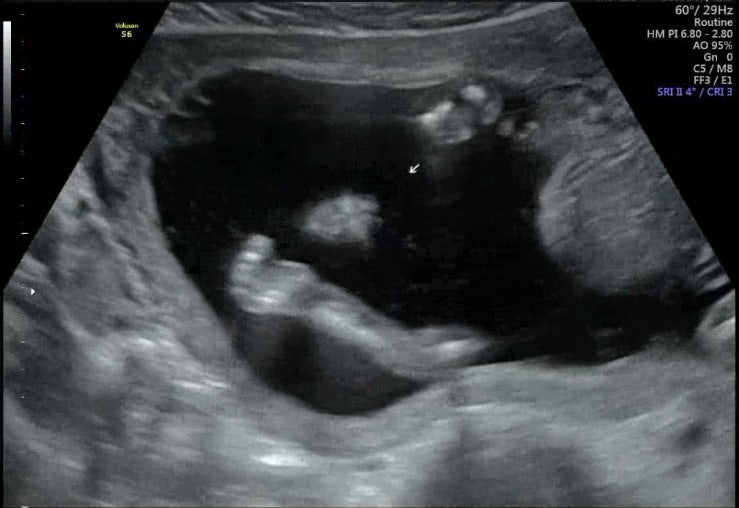

17주 2차 기형아 검사 및 니프티 신경관결손 검사후기.

17주차 2차 기형아 검사 받으러 ㄱㄱ 어제 밤 12시쯤 집에 도착해서 대충씻고 잠들었다. 정말 피곤해서 서...